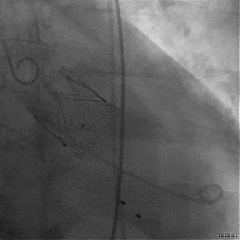

TAVR手术过程

主动脉瓣大量反流

回撤导引鞘,定位键顺利展开

输送器调弯

定位键解离

推送入窦形态改变不明显

无窦瓣叶脱垂影响瓣叶夹持

回撤后增加调弯夹持瓣叶

右窦中心造影确认瓣叶夹持

食道超声确认瓣叶夹持

经胸超声确认右冠瓣叶夹持

回撤MP导管,一键释放瓣膜

松弯后输送器回撤至大鞘,更换小鞘

术后右窦中心造影,无漏,无AVB